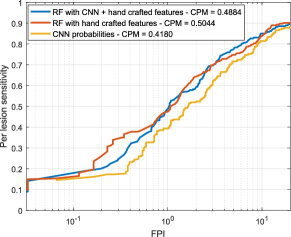

Free-response ROC (FROC) curves were used to evaluate the performance of our red lesion detection method on a per lesion basis. These plots, which are extensively used in the literature to estimate the overall performance on this task, represent the per lesion sensitivity against the average number of false positive detections per image (FPI) obtained on the data set for different thresholds applied to the candidate probabilities. Thus, FROC curves provide a graphical representation of how the model is able to deal with the detection of true lesions in all the images of the data set. We also computed the Competition Metric (CPM) as proposed in the Retinopathy Online Challenge (Niemeijer et al., 2010), which is the average per lesion sensitivity at the reference FPI values . The protocol used by Seoud et al. (2016) was followed when evaluating in DIARETDB1, as indicated in Section 3.1.

As DIARETDB1 includes labels for both MAs and HEs, it is possible to quantitatively assess the accuracy of the method to detect each type of lesion. Figure 8 illustrates the FROC curves and the CPM values obtained by the models learned in Experiment 1, when analyzing MAs and HEs separately. For MA detection, the combined approach achieves higher per lesion sensitivity values than using each approach separately ( and for the hand crafted features and the CNN, respectively), with a noticeable improvement at the clinically relevant FPI=1 value (0.2885 versus 0.202 and 0.2 for combined, CNN, and hand crafted, respectively). Moreover, the differences between the manually tuned approach and the CNN probabilities are not statistically significant. When evaluating the ability of the system to detect HEs on the DIARETDB1 test set, it is possible to see that the per lesion sensitivities are higher than those reported for MA detection. Furthermore, the hand crafted features are able to achieve better per lesion sensitivity values than the combined approach () for this specific task. At the clinically relevant FPI value of 1, however, the combined approach reports a slightly higher per lesion sensitivity compared to the manually engineered descriptors (0.4907 versus 0.4724).

Table 5 summarizes the CPM values obtained for each experiment and each feature combination, and also using each of the two recently published state-of-the-art methods. Per lesion sensitivities at FPI, which is considered a clinically relevant number of false positives (Niemeijer et al., 2010) are also provided.